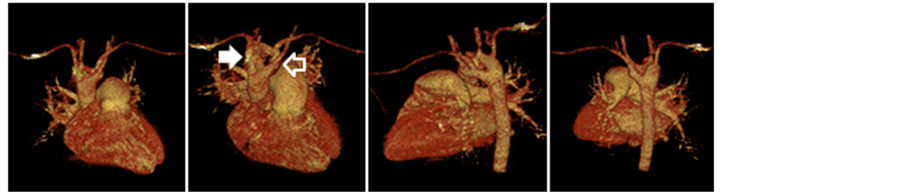

The chest CT and right cardiac catheterization revealed DAA surrounding the trachea and esophagus with right arch dominance and compression to trachea. No intracardiac defect was seen on both the CT and angiogram (Figure 2 and Figure 3). Besides DAA, chest CT results also revealed bronchiectasis. No compression of esophagus was seen in barium esophagogram. Spirometry test showed severe restrictive lung abnormalities, whereas sputum culture and antibiotic resistance test revealed Streptococcus viridans, which was sensitive to cefotaxime, cefazolin, erythromycin, and meropenem.

Figure 3. Reconstruction of patient’s chest computed tomography, right aortic arch (white arrow), left aortic arch (unfilled arrow).